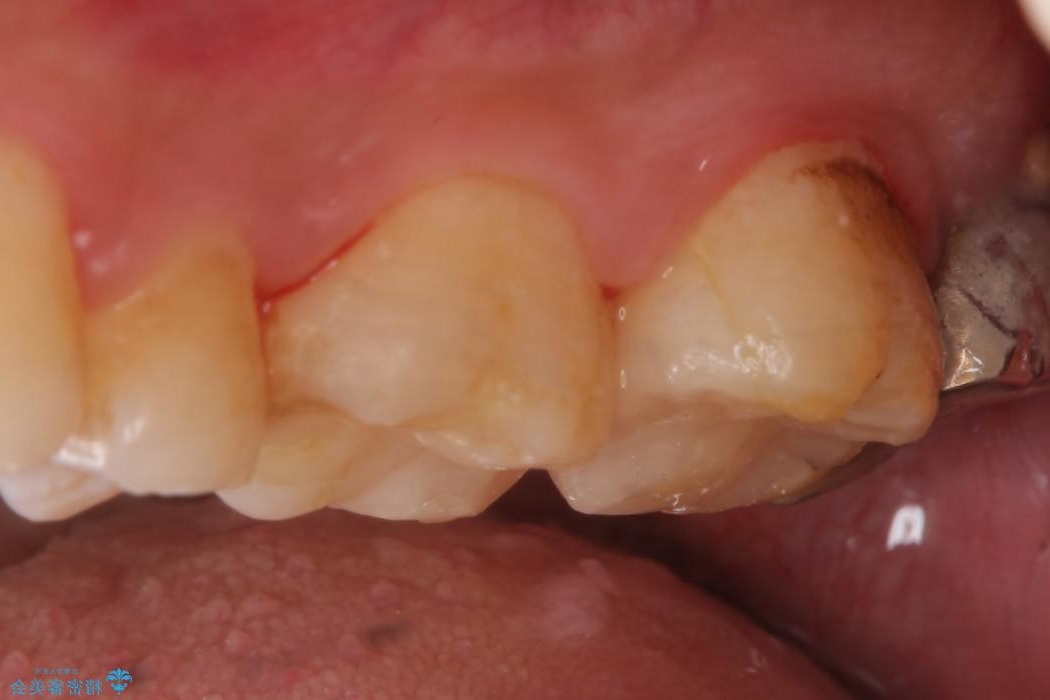

銀歯と比べて本来の歯と自然になじむ仕上がりにとてもご満足いただけました。

今回は保険で治療してあった銀歯を審美性からセラミックインレーにて再度治療しました。

セラミックスは、見た目の審美性だけでなく劣化がしにくいことや金属アレルギーのリスクがないことがメリットとしてあげられます。